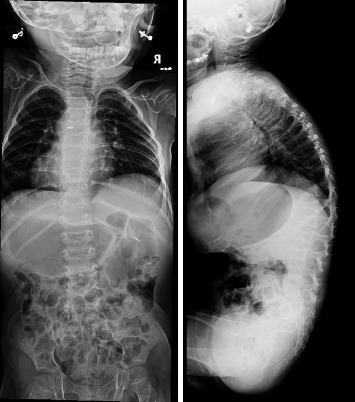

Geroderma Osteodysplastica (GO) is a rare autosomal recessive connective tissue disease characterized by wrinkled skin and osteoporosis, two distinct aging-related features. A loss of function mutation in GORAB results in the disease. Immediately after birth, a cyanotic female neonate was found to have transposition of great vessels (TGV) that was corrected with an uneventful surgical recovery. The patient was noted to have wrinkled skin and hyperlaxity in her joints. After a complete nutritional and metabolic panel, in addition to karyotyping, imaging, skin histopathology analysis, and genetic testing she was found to have GO. We found two novel compound heterozygous mutations in GORAB: p.Asp236∗ and pAsp236Ala. This is the first study that reports the concurrent incidence of GO with TGV. The patient was started on bisphosphonates, which led to a reduction in the occurrence of fractures. An early diagnosis of GO is warranted to prevent or reduce bone density loss due to osteoporosis via initiation of bisphosphonate treatment. Whole exome sequencing remains the gold standard for diagnosing GO and ruling out phenotypically similar disorders.

Abstract Image